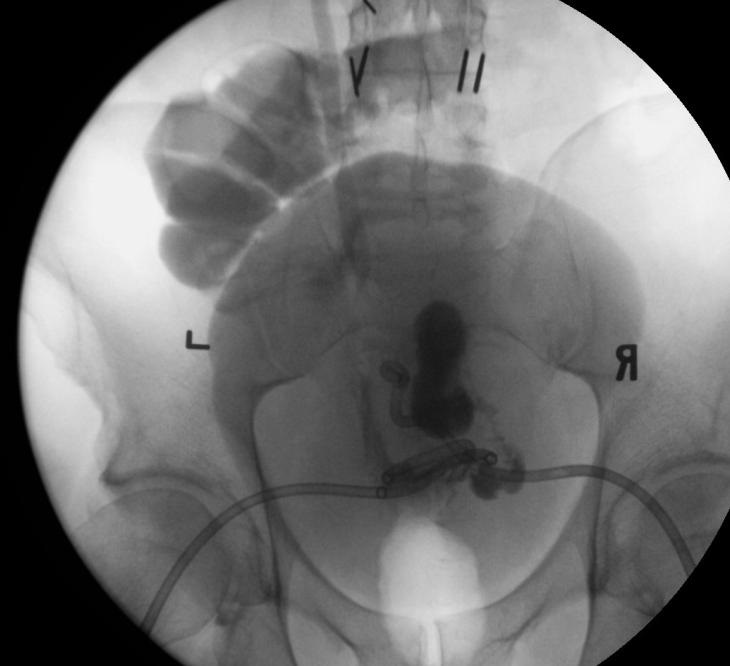

病例2 乙状结肠憩室瘘

第18天